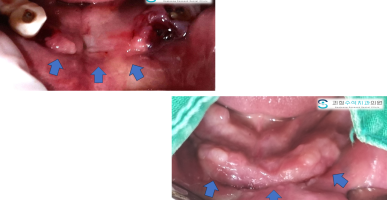

잇몸복원수술

외상으로 잇몸뼈의 형태와 잇몸의 형태가 소실된 채로 보철을 하고 계셨는데 이번 기회에 잇몸성형술을 이용하여 복원한 사례입니다.